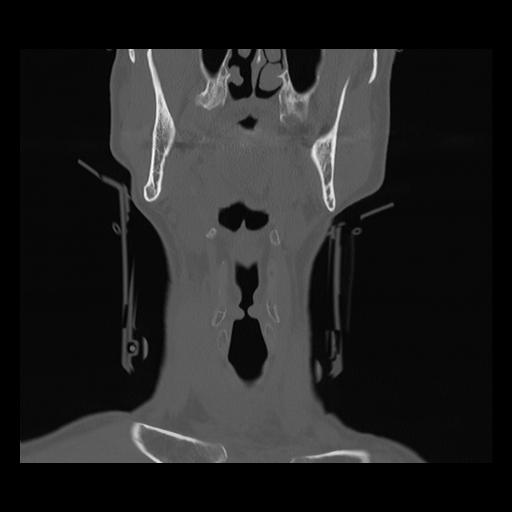

16 HUESO,,Coronal,2.000,HUESO,Coronal,